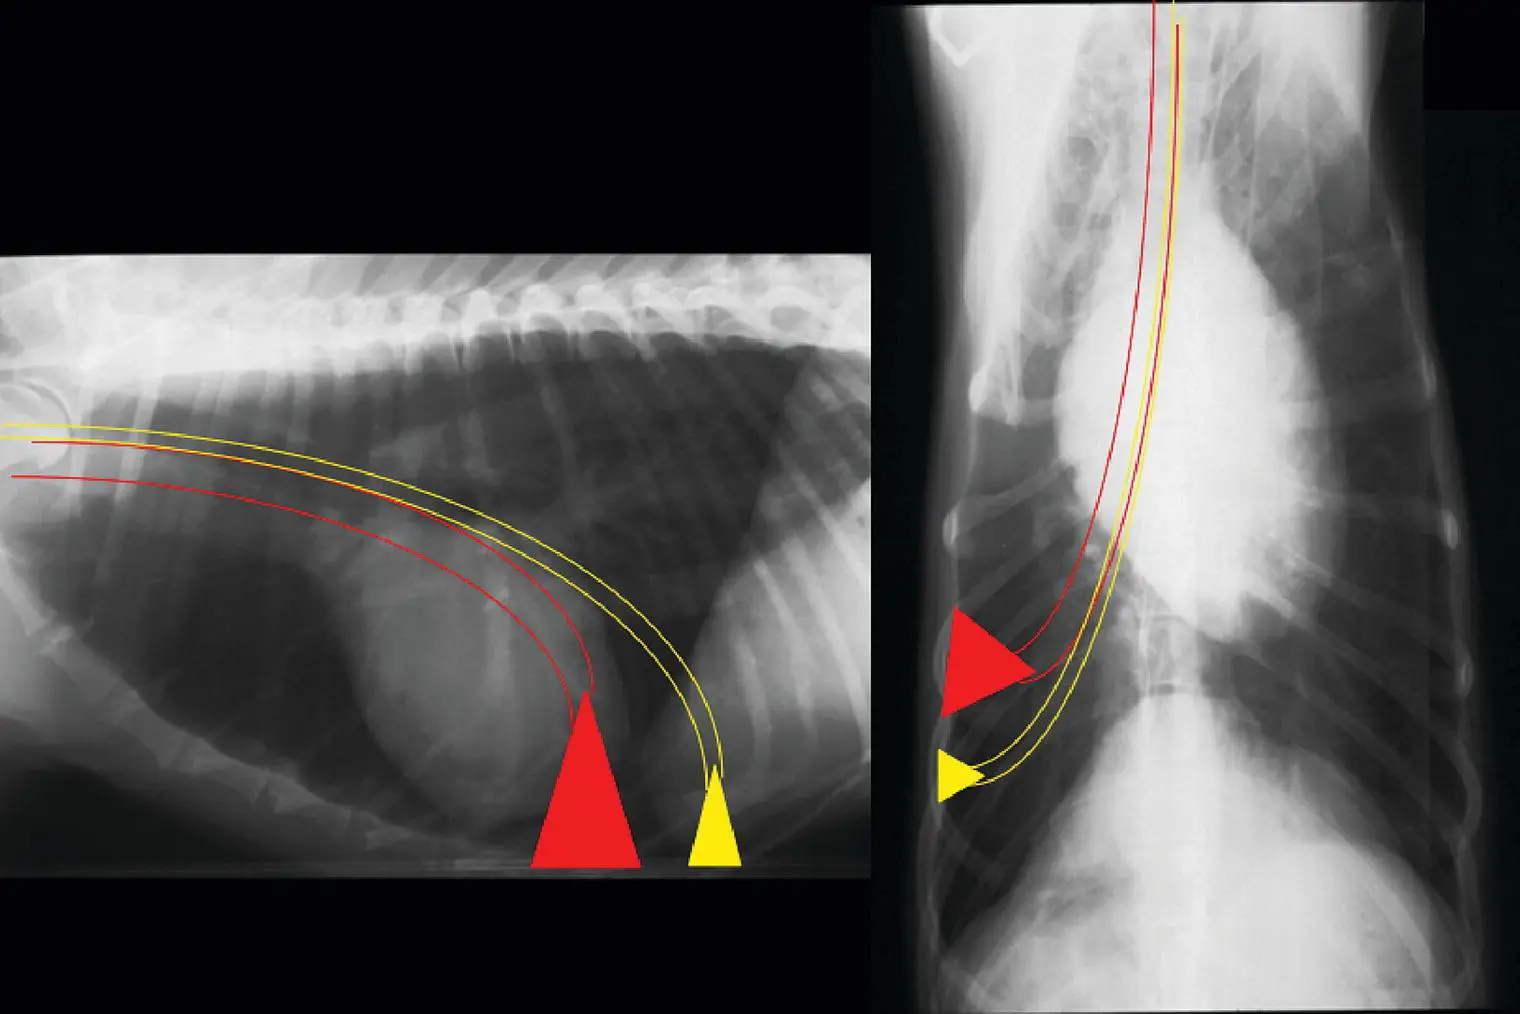

Thoracocentesis is performed as a diagnostic and therapeutic technique. It can be done before radiographs are performed when physical examination suggests a pleural disorder and the animal is in distress, after thoracic ultrasound demonstrates pleural disease, or after radiographs when pleural space disease is confirmed. The region of the seventh to ninth intercostal space is clipped and scrubbed in the ventral one‐third of the chest for fluid and in the dorsal one‐third for air. A 20 or 22 gauge butterfly needle is adequate for use in small dogs and cats when small pleural effusion or mild pneumothorax is present. A fenestrated 14–18 gauge catheter with extension set works well for larger dogs and can allow relatively rapid removal of large pleural effusions. Prior to entering the chest, an extension set, three‐way stopcock, and syringe should be assembled and ready for use to limit introduction of air into the pleural space after penetration with the needle or catheter. A large bowl, ethylenediaminetetraacetic acid (EDTA) and red‐top tubes, and a culturette swab should also be readily available to allow efficient specimen collection. In some animals, sedation is needed to perform a chest tap safely. Whenever possible, it is useful to have three people available to perform a chest tap.

A sterile preparation of the lateral thorax is completed and a site on the chest wall is chosen. The needle or catheter is advanced through tented skin and then walked off the cranial border of the rib to penetrate the pleural space at a perpendicular angle. This will avoid the vessels and nerves lying along the caudal rib margin. As soon as the pleura has been penetrated, the needle or catheter is directed downward to avoid injury to the lung parenchyma ( Figure 2.23). The needle stylet is held stationary while catheter is advanced over the needle into the pleural space. When the catheter is fully in the chest, the needle is withdrawn, and the extension set is rapidly attached.

Figure 2.23 (a) To initiate thoracocentesis, the skin is tented and the catheter with needle is inserted perpendicularly between the rib spaces. (b) After the pleural space has been entered, the needle is directed ventrally and the catheter is advanced fully into the chest while the needle is held stationary.